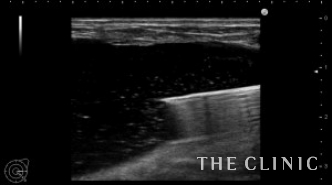

本日は横浜院でヒアルロン酸のしこり除去を行いました。

吸引後です。ヒアルロン酸は消失しました。

ヒアルロン酸注入によるしこりのエコー診断カルテ